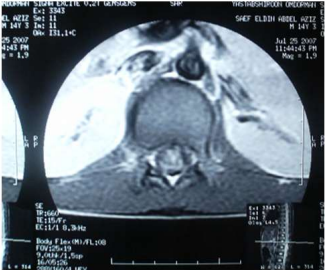

Eight of the ten patients were diagnosed utilizing MRI which showed Dorsal 12 to Lumber 1 or 2 spinal cord swelling with hyper intense patches in T2 images , while the remaining two patient were diagnosed utilizing CT myelogram which showed Dorsal 12 to Lumber 1 or 2 spinal cord swelling.

Image (3) Axial MRI of case (1) T1 weighted MRI showing spinal cord expansion and scattered hyperintense patches.

Images (4 & 5) MRI of Case No (6). Showing cauda equina expansion and hyperintense patches of in the cauda equine of both T1 and T2 weighted MRI.

Image (6) Axial MRI of case (6) T1 weighted MRI showing spinal cord expansion and scattered hyperintense patches.